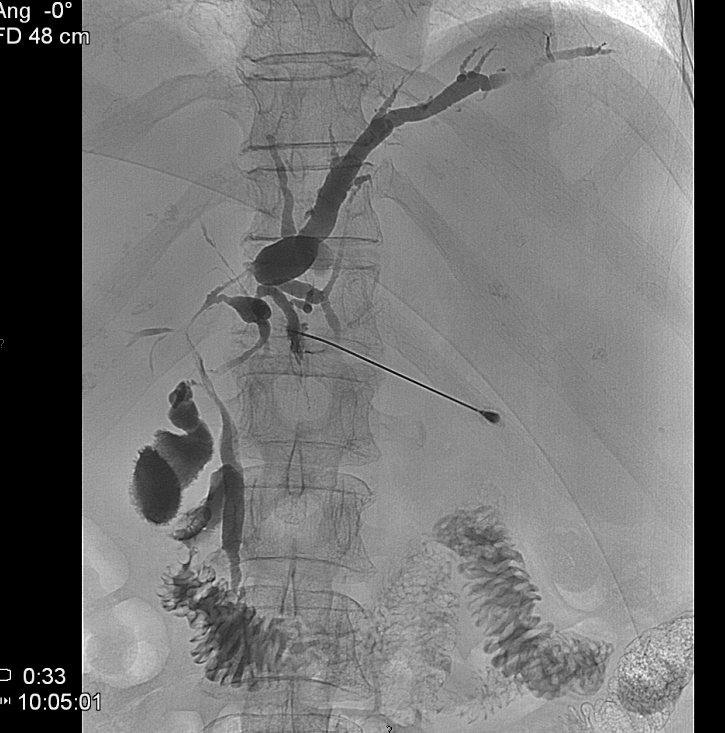

During this procedure X-ray or US is used to guide the insertion of a 22G (Chiba needle) from a right IX. or X. intercostals position into a dilated intrahepatic biliary branch. After the Chiba needle is well positioned the intra and extrahepatic biliary tree is filled with contrast material. (Figure 21.)

Under special circumstances – when the left side of the biliary branches is affected primarily - PTC can be performed from an epigastric entry towards the left lobe of the liver. (Figure 22.)

Image

Figure 21. – PTC (Percutaneous transhepatic cholangiography)

Figure 22. – PTC the puncture of the biliary branches of the left lobe

19.5.2. Percutaneous transhepatic drainage (PTD)

After a diagnostic PTC is successfully performed and a guide wire is positioned over the stenotic or occluded segment of the choledochal duct an external-internal drain (PTD) can be installed. (Figure 23.) If desired, a self expanding metallic stent could be used to override the stricture (Figure 24.)

Figure 23. – PTD (Percutaneous transhepatic external-internal drainage)

Figure 24. – Choledochal stent, palliative procedure do pancreatic head tumor